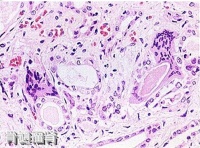

骨髓瘤肾(显微镜下图片)

骨髓瘤细胞(低倍镜所见)

镜下可见瘤体主要由大量密集的瘤细胞组成,间质极少。瘤细胞多呈圆形或卵圆形,但具有不同程度的幼稚性。按分化程度的差异,可分为高分化型(小细胞型)及低分化型(大细胞型)两种。前者分化较成熟,体积小,具有圆形而偏心性的核,染色质呈车轮状,亦称浆细胞型骨髓瘤;后者分化差,体积大,有时有双核,核仁明显,核分裂较多见,亦称网状细胞型骨髓瘤。